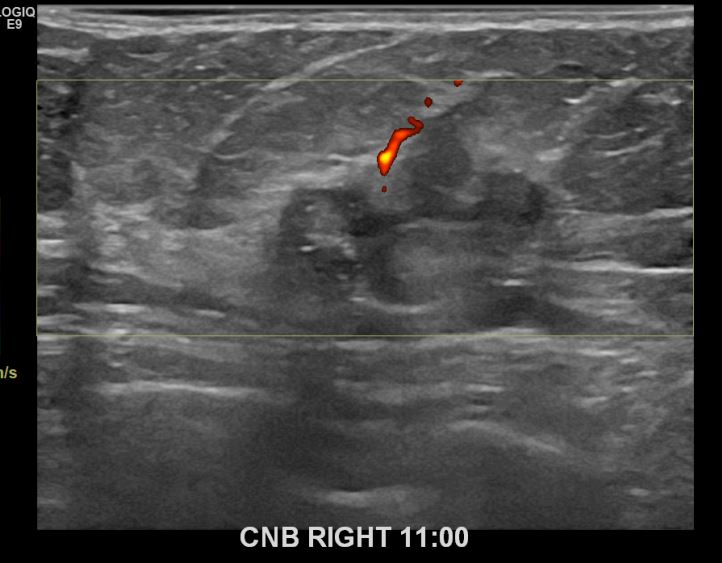

상기환자 건진상 이상소견으로 조직검사권유받고 내원하신 50대 여성분으로 우측유방멍울  조직검사시행후 유방암 진단되었습니다.